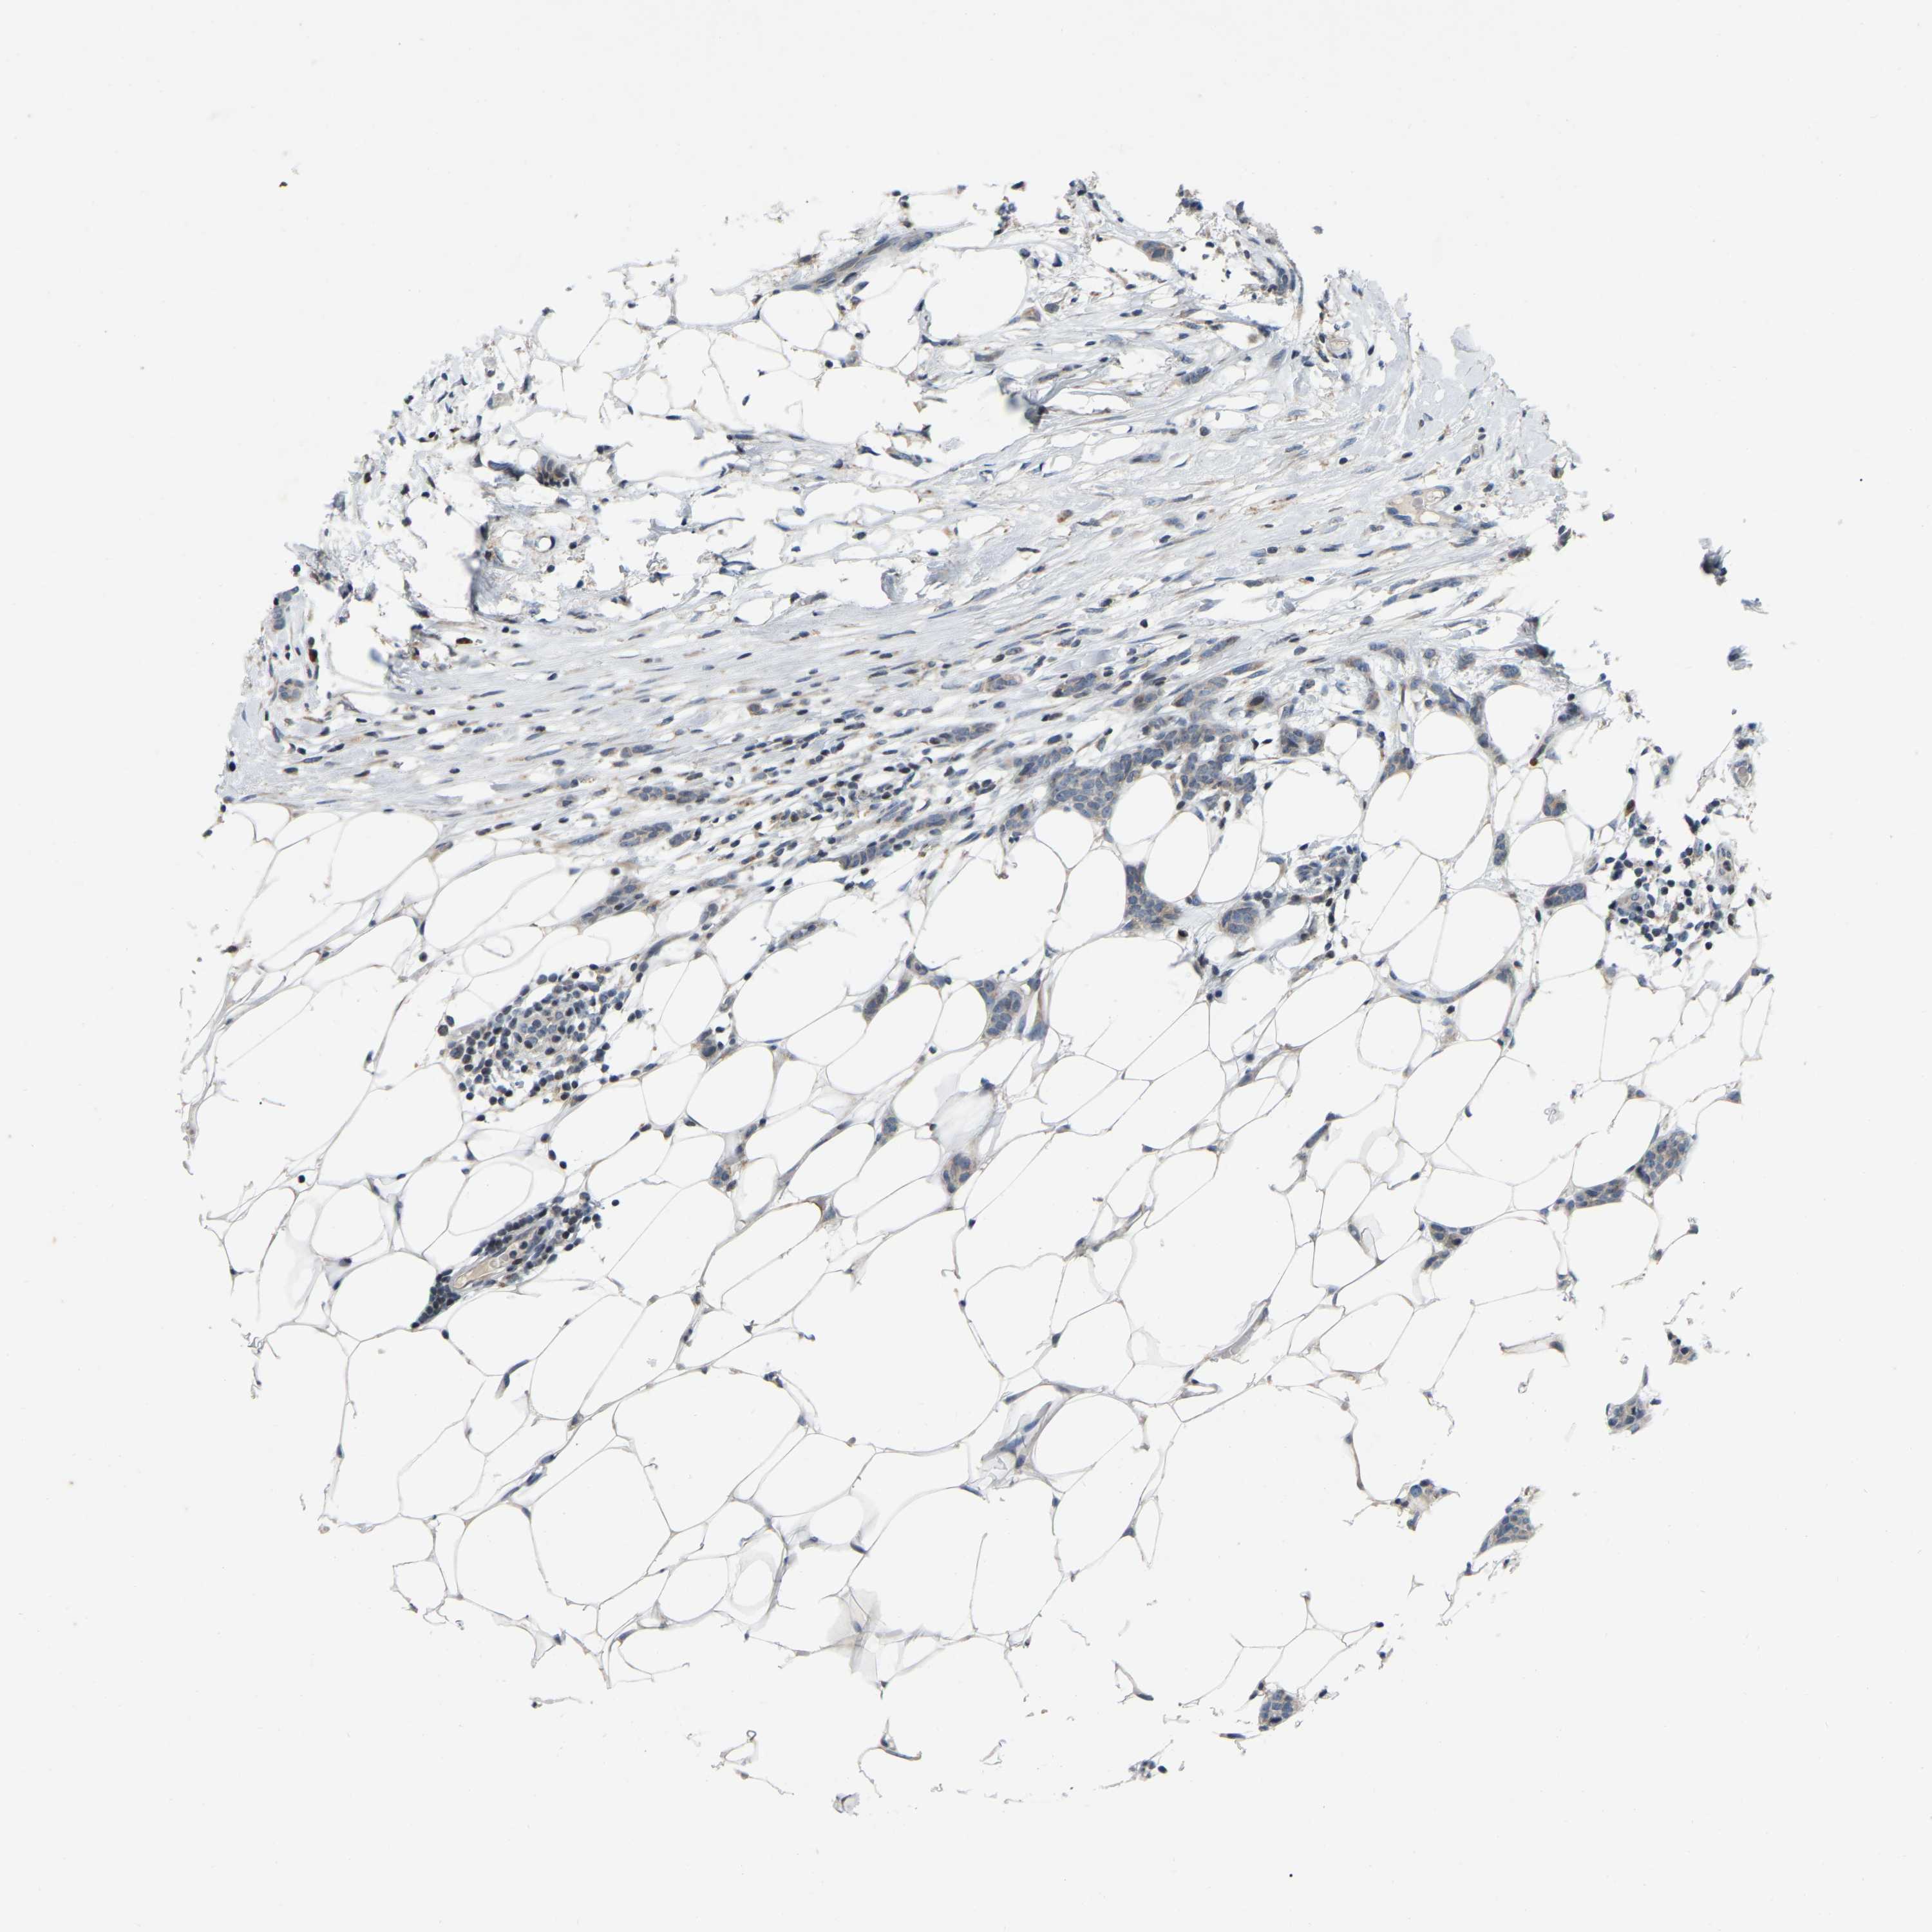

Breast cancer

Human cancer